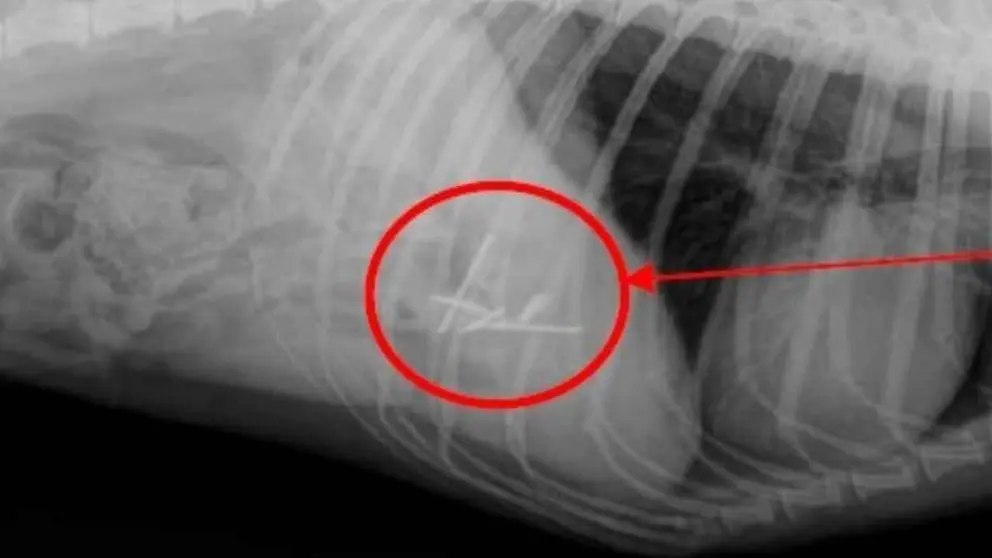

Radiografía del tracto digestivo del perro en la que se aprecian los clavos. POLICÍA FORAL

Como consecuencia de estos hechos, una perra ingirió uno de los cebos. Tras ser trasladada a un centro veterinario, las pruebas radiográficas confirmaron la presencia de cuatro clavos en su tracto digestivo.